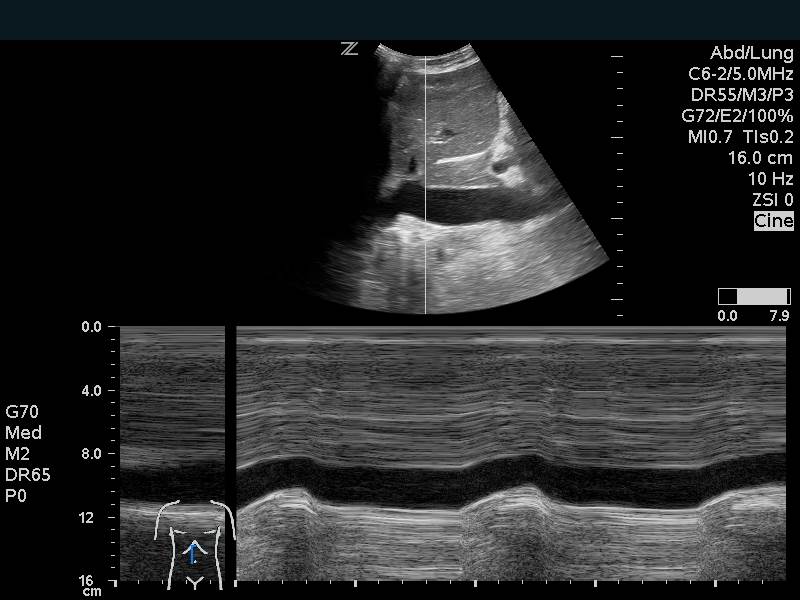

The IVC can be used as a measure of volume responsiveness, although this is more accurate in mechanically ventilated patients than in those spontaneously breathing.8,14,15 This is likely most helpful in the extremes. A patient with a small IVC that is highly collapsible would likely benefit from fluids. M-mode can be used to measure inspiratory and expiratory diameters although caution must be taken to prevent measuring the IVC at inconsistent points due to overall movement from breathing. A patient with a large IVC that has no change in diameter with respirations, is less likely to benefit. Keep in mind that a large plethoric IVC will be present in signs of obstructive shock and any cause of elevated right sided cardiac pressures.

Figure 12. Inferior Vena Cava Respiratory variation on M-mode